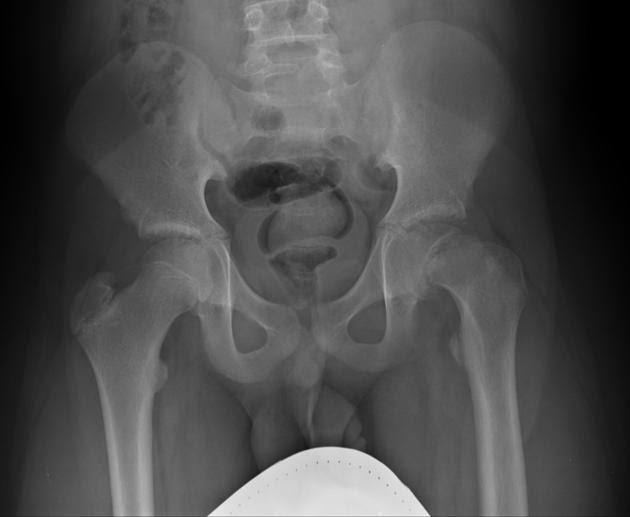

(“infant” is defined as under 1 year old only) ap and lateral hip to ankle (include entire pelvis on ap to provide comparison view of opposite hip). This is necessary to make the diagnosis or to be sure the hip is normal. True positioned films are necessary, especially at knee and ankle. The condition can, however, be present in both.

(“infant” is defined as under 1 year old only) ap and lateral hip to ankle (include entire pelvis on ap to provide comparison view of opposite hip). How do they x ray babies hips. The condition can, however, be present in both hips. They can penetrate your body. Can hip dysplasia correct itself?

(“infant” is defined as under 1 year old only) ap and lateral hip to ankle (include entire pelvis on ap to provide comparison view of opposite hip). According to the international hip dysplasia institute, 1 in 10 infants are born with hip instability, meaning the hips can be wiggled in the. This is necessary to make the diagnosis or to.